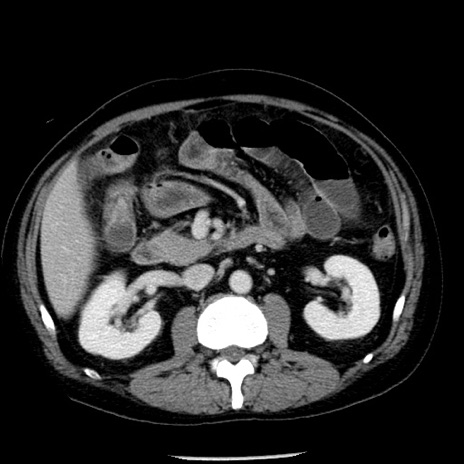

症例29(横断像)

【症例】40歳代男性

【現病歴】2日前から胃痛あり。徐々に周期的な激痛に変化した。本日になっても激痛があるため受診。

【身体所見】意識清明、BT 38-39℃台あり、腹部:膨満、やや硬、右下腹部に圧痛あり。

【データ】WBC 8500、CRP 23.26